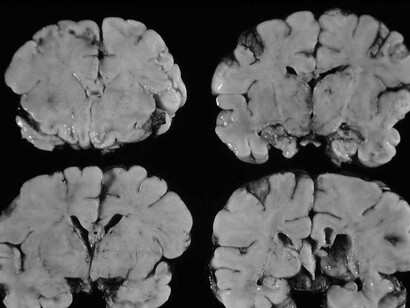

El mecanismo inicial de infección parece ser el reconocimiento y fusión por parte de la proteína S denominada espiga (spike) de la superficie del SARS-CoV-2 con el receptor para la enzima convertidora de angiotensina 2 (ACE2) en humanos; esta última expresada en el endotelio capilar del cerebro y multitud de órganos. En relación con esta información, recientemente se ha demostrado la presencia de SARS-CoV-2 en muestras de autopsias a nivel del SNC en los revestimientos endoteliales en las áreas adyacentes a las áreas necróticas en pacientes enfermos de COVID-19. Además, se ha aislado SARS-CoV-1 del tejido cerebral con edema neuronal y degeneración a partir de autopsias. Todo esto se ha llevado a cabo con métodos de inmunohistoquímica, hibridación in situ y confirmación microscópica electrónica de la infección viral de neuronas.